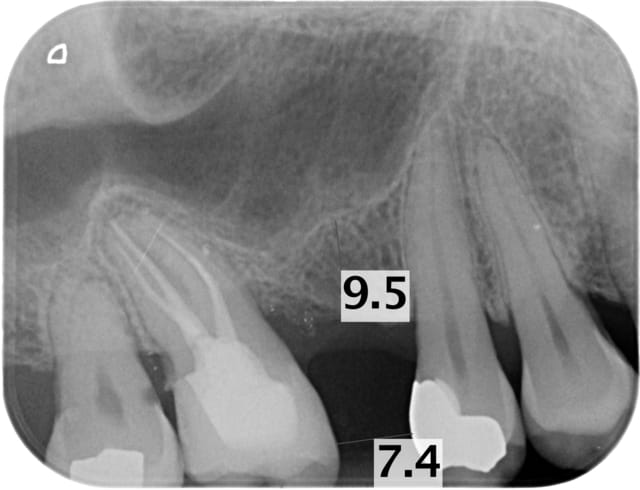

Voici des exemples pour que tu puisses comparer

vistascan 20pl/mm

70Kv, 8mA, 0.16s

Montre nous tes radios qu'on puisse comparer aussi